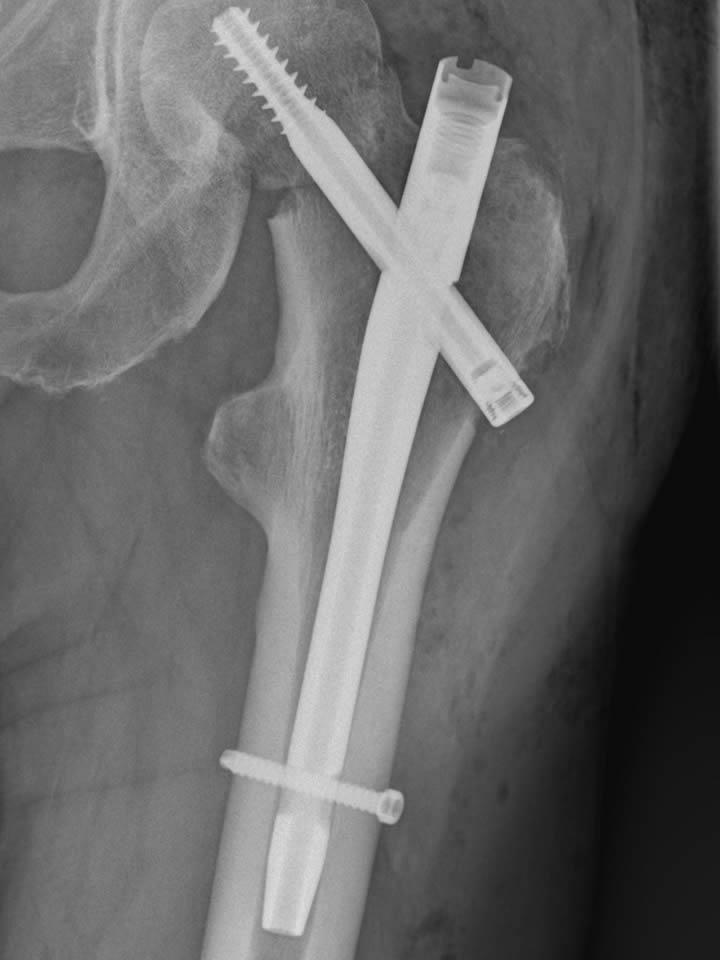

Bei der Visite am 10.07. frage ich mal unbedarft nach, wann in der nächsten Woche denn die Kontrollröntgenaufnahme gemacht wird und erfahre, dass die Röntgenabteilung nächste Woche im Urlaub ist und wir das Bild dann heute noch schnell machen. Am Nachmittag bin ich also zum Fototermin, der mein Leben mal wieder verändern wird, aber das weiß ich ja noch nicht. Erst weit nach dem Abendessen werde ich zum Chefarzt gerufen und der Tag ist gelaufen. Auf dem Bild ist deutlich erkennbar, dass die Schraube durch den Knochenkopf gekommen ist und spätestens beim Laufen unter Volllast in die Gelenkpfanne stoßen wird. Der Chefarzt telefoniert noch mit der Klinik in Eilbek und danach ist klar, dass dies zunächst mein letzter Tag in St. Peter-Ording sein wird.

Am nächsten Tag sitze ich um 12°° Uhr im Taxi nach Hamburg und kurze Zeit später bestätigt mir auch der hiesiege Facharzt, dass ich nun eine Hüftprothese brauche. Gottseidank hatte ich kein Mittag, denn ich hätte gar nicht so viel essen können, wir ich kotzen könnte. Für mich bricht nach 5 Wochen mit guten Fortschritten, viel Arbeit in der Reha und einigen längeren Spaziergängen, eine Welt zusammen und ich bin einem Nervenzusammenbruch nahe.

Im Krankenhaus wird schnell klar, dass mein Oberschenkelhals gebrochen ist und ich noch in der Nacht operiert werde. Als ich erwache ist es früh morgens, 4°° Uhr und ich schlafe gleich noch ein paar Stunden weiter. Nach dem zweiten Erwachen gibt es gleich mal einen Kaffe und die üblichen Morgenrituale auf Krüppelniveau und dann geht's zum Röntgen. Zwei Stunden später kommt schon wieder jemand, um mich zur CT zu bringen. Würde man immer eine CT machen, wenn man einen Oberschenkelhals repariert hat, hätte man das gleich gemacht, also muss es einen anderen Grund geben. Den erfahre ich wenig später, als mein Arzt mir eine zweite Operation für morgen früh avisiert. Der Knochen muss noch etwas justiert, sprich um einige Grad verdreht werden. Mir geht es ziemlich mies. Laufen ist ja eher meine physiologische Kernkompetenz und auch sonst irgendwie von zentraler Bedeutung.

Der nächste Tag wird auch nicht besser! Zwar verläuft die OP gut und ich bin Mittags wieder bei Sinnen, doch dann kommen die nächsten Hiobsbotschaften. Das geflickte (genagelt und verschraubt) Bein darf ich für die nächsten 6 Wochen nur mit 50% belasten, d.h. 6 wochen an Krücken! Auch, wenn ich abends wenigstens wieder selbst auf die Toilette gehen kann, ist das der 3. Tag in Folge ganz im unteren Bereich auf der Skala des Leidens.